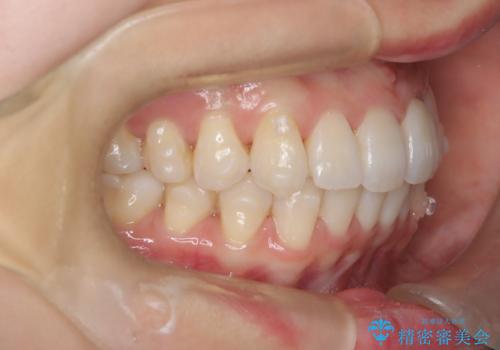

インビザラインモデレートによる前歯の叢生改善|IPR最小限で自然な歯並びへ

- 患者様は、**前歯の叢生(がたつき)**を気にされて来院されました。

できるだけ歯を削らずに、自然な歯並びを手に入れたいというご希望がありました。

診査の結果、中等度の叢生であったため、インビザラインモデレートでの対応が可能と判断しました。

歯へのダメージを抑えるため、IPR(歯間削合)は必要最小限にとどめる方針としました。

前歯の叢生は解消され、自然で調和の取れた歯並びが得られました。

「歯をほとんど削らずにきれいになった」と、患者様にもご満足いただけました。